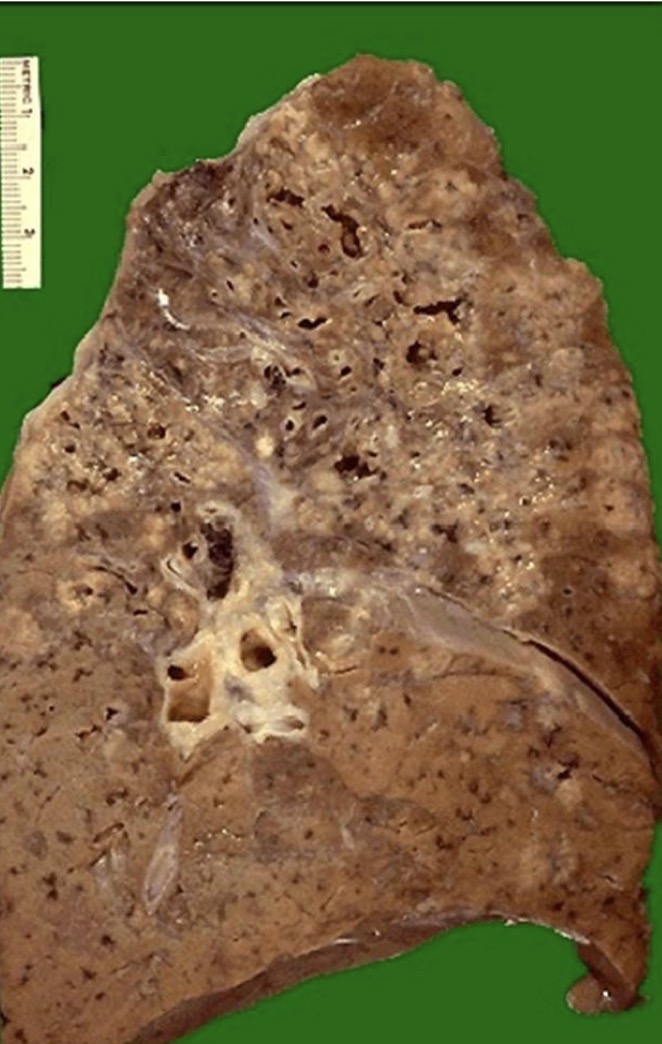

A- identify

B- describe

A- Granulomatous inflammation

B- Showing numerous confluent granulomas in upper

lung fields in a case of active pulmonary tuberculosis